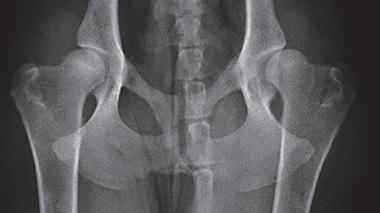

Displasia de cadera (I): etiopatogenia, signos clínicos y pruebas diagnósticas 26